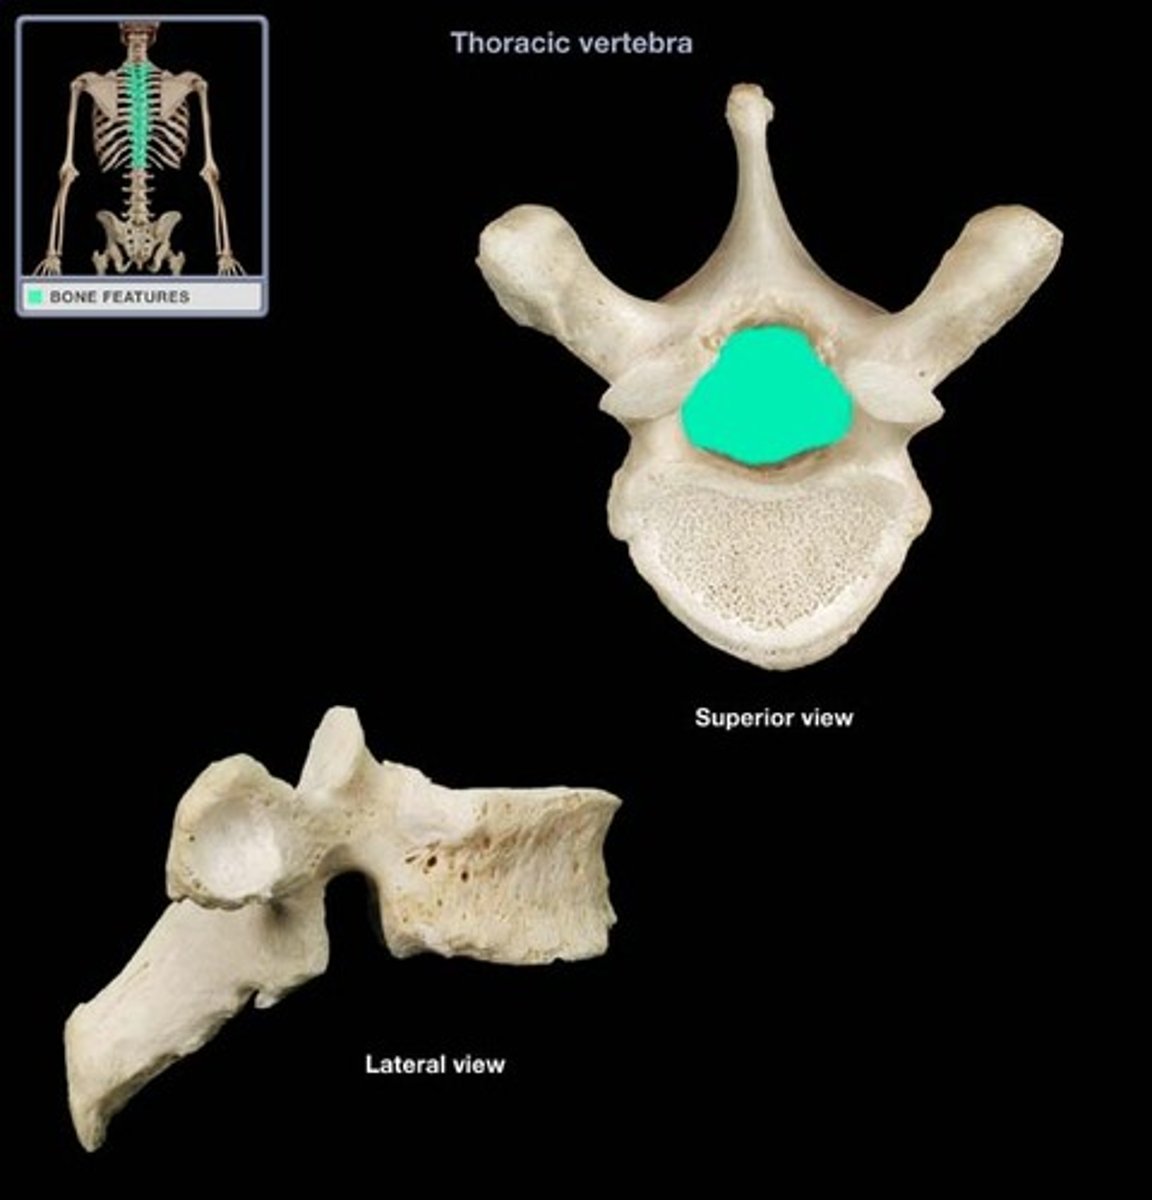

transverse process

vertebral formen

pedicle

body of vertebra

spinous process

transverse costal facet

rib articulation (attachment) ONLY FOUND IN T1-T12

transverse costal facets (articulations) where ribs attach to

what differenciates the T spine vertebra